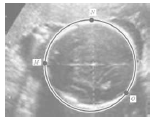

A figura representa a cabeça de um bebê num exame desse tipo. Através de recursos computacionais, define-se uma circunferência num sistema de coordenadas cartesianas através de três pontos:

M(−3,3), N(2,8) e O(6,0).

O comprimento dessa circunferência corresponde ao que os médicos chamam de perímetro cefálico. No caso indicado na figura acima, por um problema técnico, o computador não indicou o comprimento da circunferência. Sabe-se que cada unidade linear do plano cartesiano que contém a figura corresponde a 1 cm na medida real.